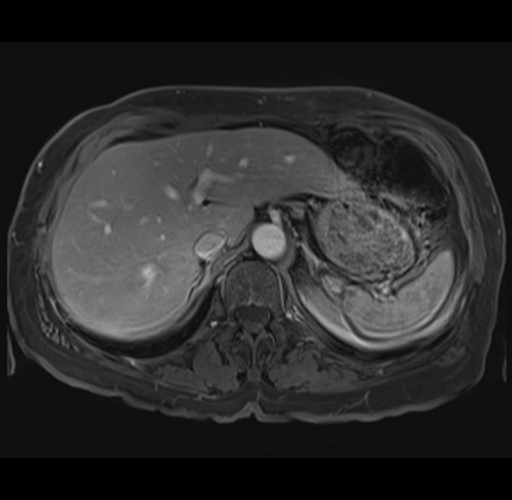

MRI T1

Imaging analysis